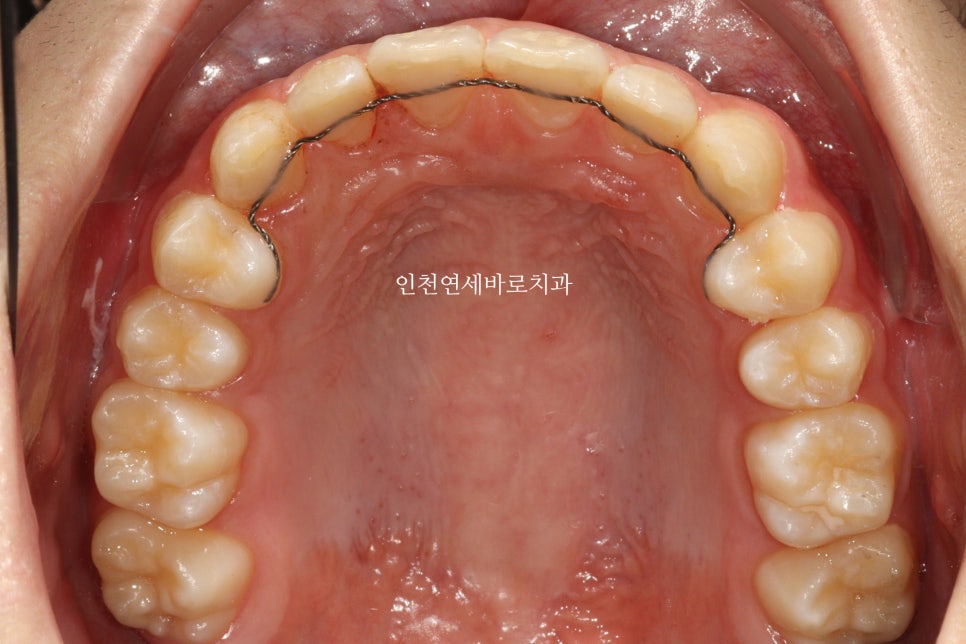

치료 전과 후 입니다.

앞니가 후방이동 한것이 확인됩니다.

우리는 부분교정을 한것이 아니라 간단한 전체교정을 한것입니다.

전과 후의 얼굴 변화입니다.

치아가 들어가보입니다.

앞니만 철사를 붙여서는 얻기 어려운 결과라고 생각합니다.